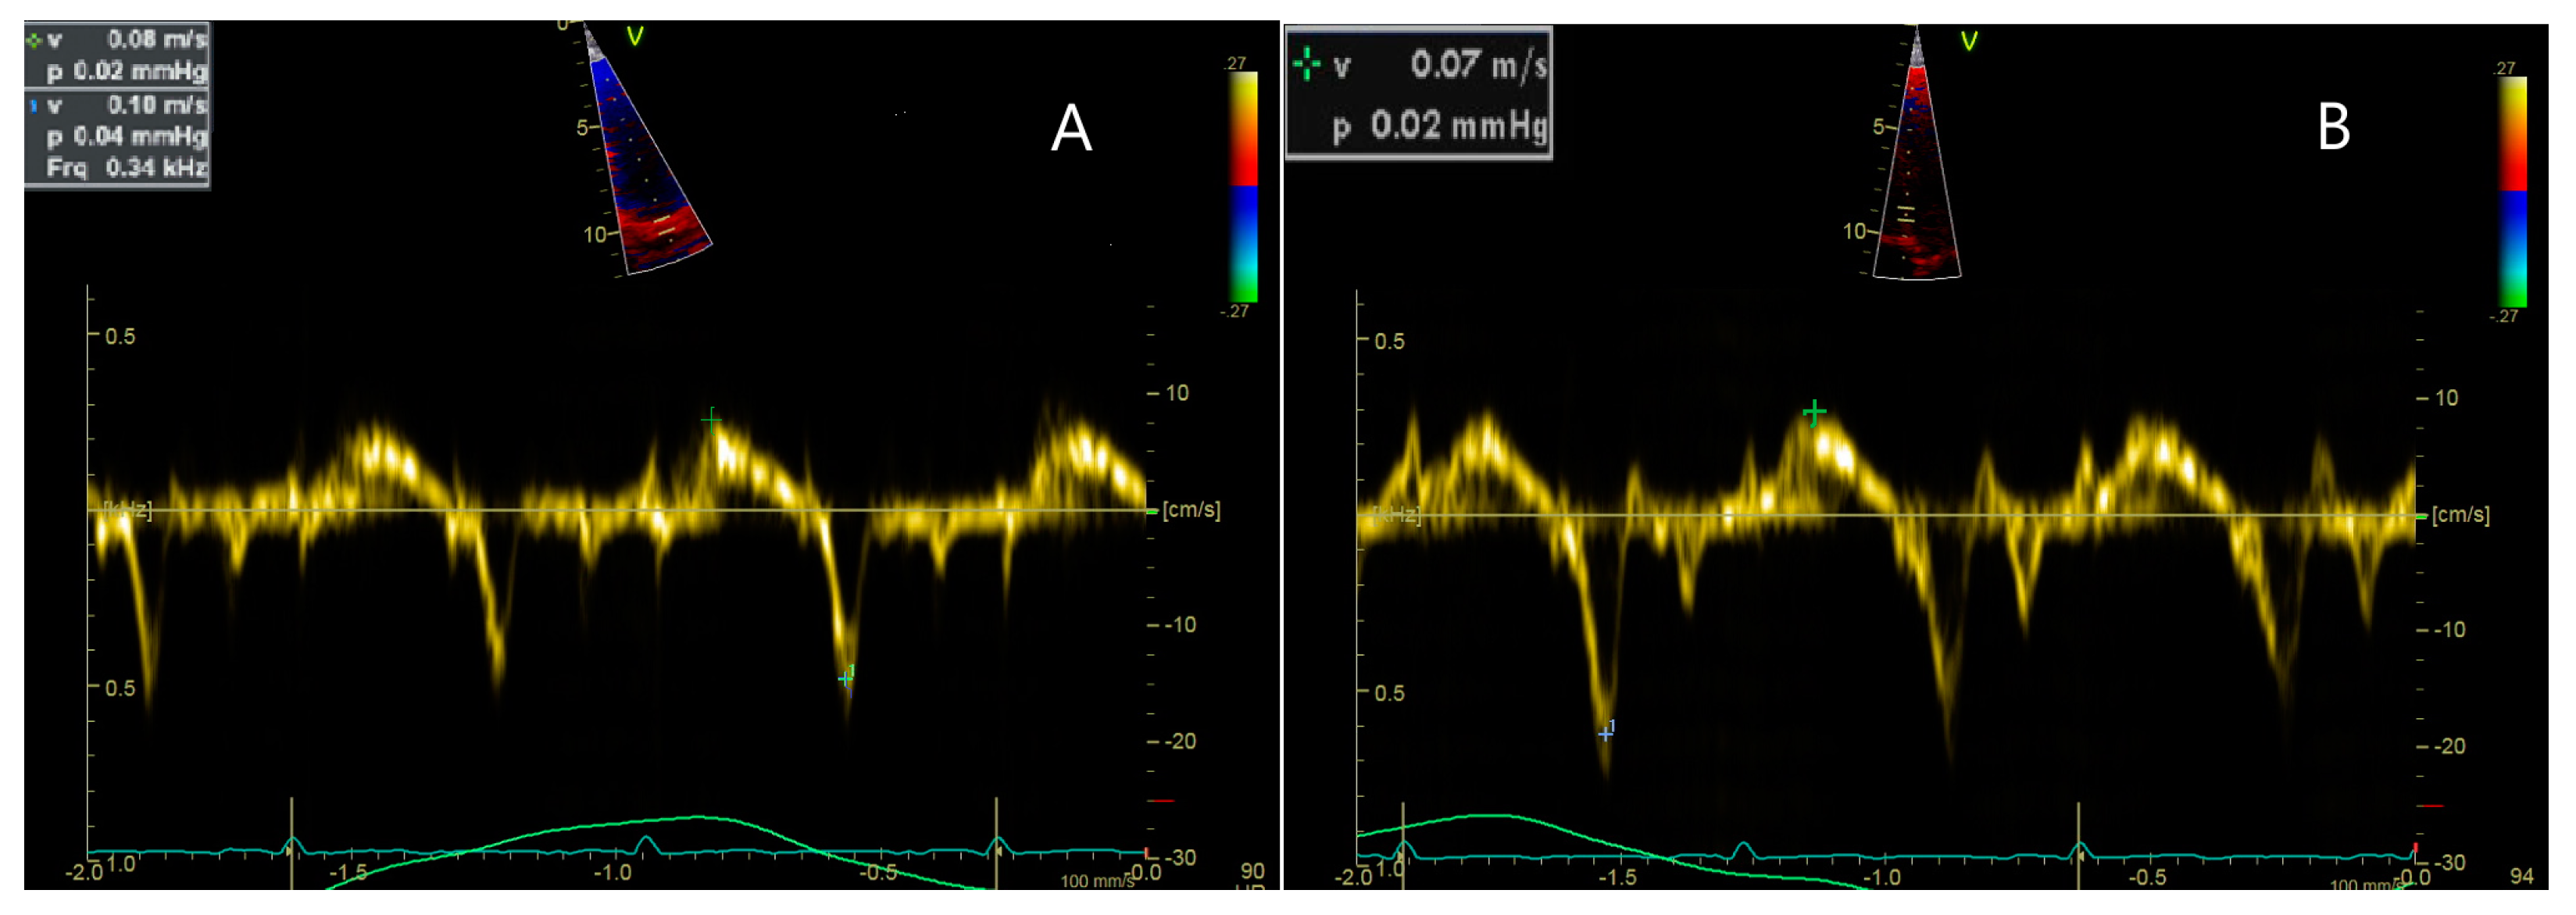

| 8 y 1 m | Longitudinal dysfunction of the LV and RV. EKG: Sinus tachycardia with HR = 100 bpm, QRS axis at 0 degrees, juvenile ST-T pattern. |

| 9 y | LV slightly globular with normal global systolic function. Normal diastolic function. No valvulopathies. No pulmonary hypertension. BP = 100/60 mmHg; HR = 75 bpm; no murmurs. EKG: Sinus rhythm with HR = 90 bpm, QRS axis = +45 degrees, PR interval = 0.12 s, juvenile ST-T pattern. |

| 10 y 5 m | LV globular. Longitudinal dysfunction of the LV. BP = 100/60 mmHg, HR = 90 bpm, grade I/VI systolic murmur heard at the left parasternal border. EKG: RBBB. |

| 11 y 4 m | LV globular with preserved ejection fraction. Longitudinal dysfunction of the LV. EKG: Sinus tachycardia HR = 110 bpm, QRS axis +60 degrees, PR interval: 0.18 s, RBBB with secondary ST-T changes. |